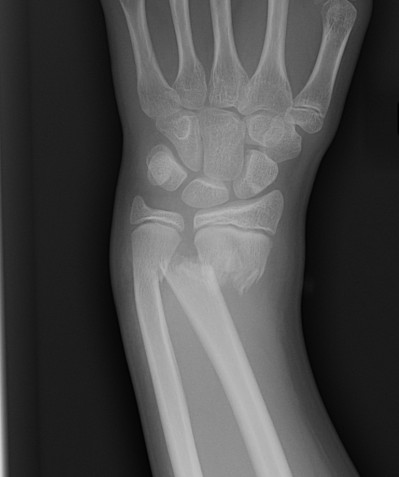

Incidence

Metaphyseal > physeal / SH2

Aetiology

FOOSH